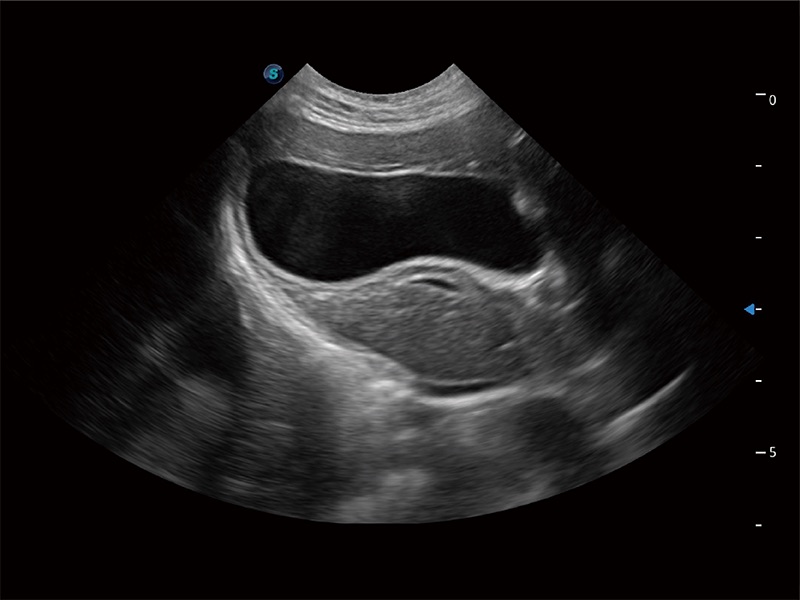

高性能和先進的臨床應(yīng)用工具可以為動物醫(yī)生提供臨床信心。ProPet 80 搭載了先進的腹部和淺表應(yīng)用工具,幫助醫(yī)生在日常臨床實踐中發(fā)揮前所未有的作用。

ProPet 80 專為動物醫(yī)生設(shè)計,對不同的動物體型和生理結(jié)構(gòu)作出了針對性的優(yōu)化。通過動物影像專用軟件,可滿足個性化的應(yīng)用需求,幫助動物醫(yī)生獲得更精確的診斷數(shù)據(jù)。

為精細結(jié)構(gòu)及組織邊緣提供高清晰度的圖像和更大的成像視野。幫助減輕醫(yī)生的用眼疲勞,快速精準獲得測量的數(shù)據(jù)。

ProPet 80 全新的動物超聲智能軟件和豐富的探頭群,為動物醫(yī)生提供了高清晰度和精細分辨率的圖像,無論在寵物、馬科、畜牧還是實驗室動物等應(yīng)用中都可以輕松應(yīng)對,為您的日常工作帶來滿意的體驗。